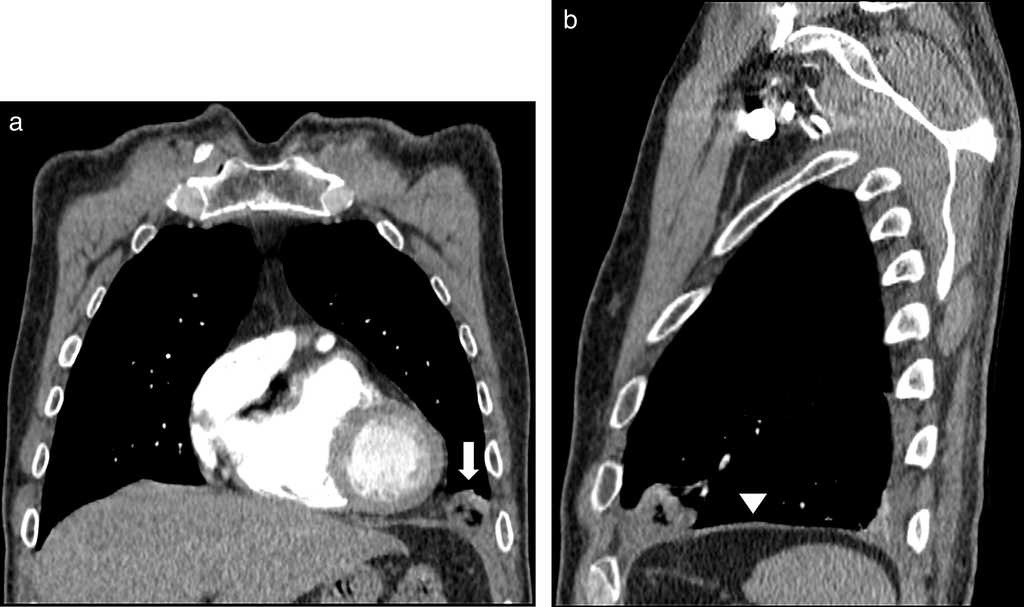

El segundo caso fue un var??n de 67 a??os de edad, sin antecedentes patol??gicos, que consult?? a urgencias por un cuadro de dolor tor??cico opresivo e intenso, de una hora de evoluci??n, que se irradiaba al hemit??rax izquierdo y se asociaba a n??useas y disnea. El electrocardiograma y troponinas fueron normales. Se realiz?? una angiograf??a por TC de t??rax que evidenci?? una lesi??n redondeada con atenuaci??n central grasa y de mayor densidad perif??rica, localizada en la grasa epic??rdica anterior hacia el ??ngulo cardiofr??nico izquierdo (fig. 2). Esto se relacionaba con una torsi??n del cojinete graso epic??rdico con infarto. No se encontr?? tromboembolismo pulmonar ni alteraciones del par??nquima.